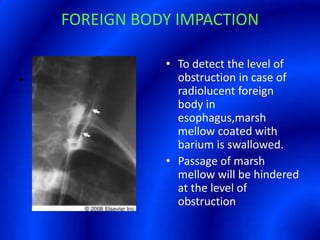

This document provides information about a barium swallow procedure. It begins with an introduction and overview of the embryology and anatomy of the pharynx and esophagus. It then describes the procedure itself, including preparation, technique, views obtained, and indications. Specific conditions that may be examined include pharyngeal and esophageal webs, foreign body impaction, scleroderma, dysphagia, mediastinal masses, and carcinoma. Diagrams are provided to illustrate normal anatomy and various pathological findings.